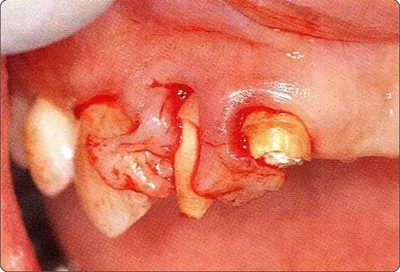

深牙周袋的治療

圖10-4  骨缺損部位進行骨修整結(jié)束的狀態(tài)。

圖10-5  利用Osseous coagulum trap,在下頜磨牙后墊三角部采取的自體骨。

圖10-6  進行自體骨移植后的狀態(tài)